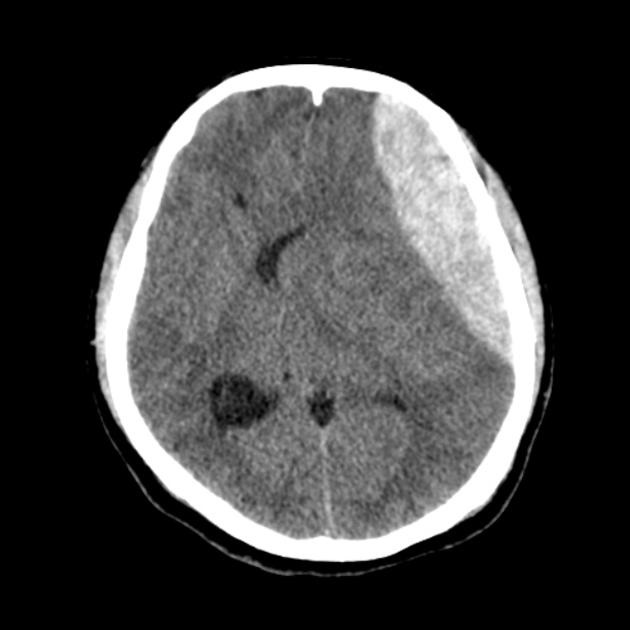

Τραυματικό αιμάτωμα ονομάζεται η παρουσία αίματος μέσα στην κοιλότητα του κρανίου μετά από μια κάκωση κεφαλής. Στην αντίθετη περίπτωση, δηλ. όταν δεν υπάρχει κάκωση, το αιμάτωμα ονομάζεται αυτόματο, όπως αναλύεται στην ενότητα εγκεφαλική αιμορραγία. Το αιμάτωμα μπορεί να βρίσκεται έξω από τον εγκέφαλο και να τον πιέζει (υποσκληρίδιο ή επισκληρίδιο αιμάτωμα) ή μέσα στον εγκέφαλο (τότε ονομάζεται αιμορραγική θλάση).

Ο εγκέφαλος περιβάλλεται από μια μεμβράνη που ονομάζεται σκληρά μήνιγγα. Αν το αιμάτωμα εμφανιστεί πάνω από τη σκληρά μήνιγγα, ονομάζεται επισκληρίδιο. Αν εμφανιστεί από κάτω, ονομάζεται υποσκληρίδιο αιμάτωμα. Τα δύο είδη αιματωμάτων έχουν ορισμένες διαφορές (πχ το επισκληρίδιο αναπτύσσεται συνήθως ταχύτερα, το υποσκληρίδιο συνοδεύεται συχνότερα και από εγκεφαλική βλάβη) ωστόσο, σε γενικές γραμμές και τα δύο χρειάζονται συνήθως επείγουσα νευροχειρουργική επέμβαση για να αφαιρεθούν.

Ένα αιμάτωμα μπορεί να πιέζει τον εγκέφαλο και να απειλεί την ίδια τη ζωή, να προκαλεί νευρολογικό έλλειμμα πχ παράλυση στο χέρι ή και το πόδι, δυσκολία στην ομιλία ή και να προκαλεί επιληπτικές κρίσεις.

Η επέμβαση για ένα αιμάτωμα εγκεφάλου συχνά γίνεται σε επείγουσα βάση για να σωθεί η ζωή